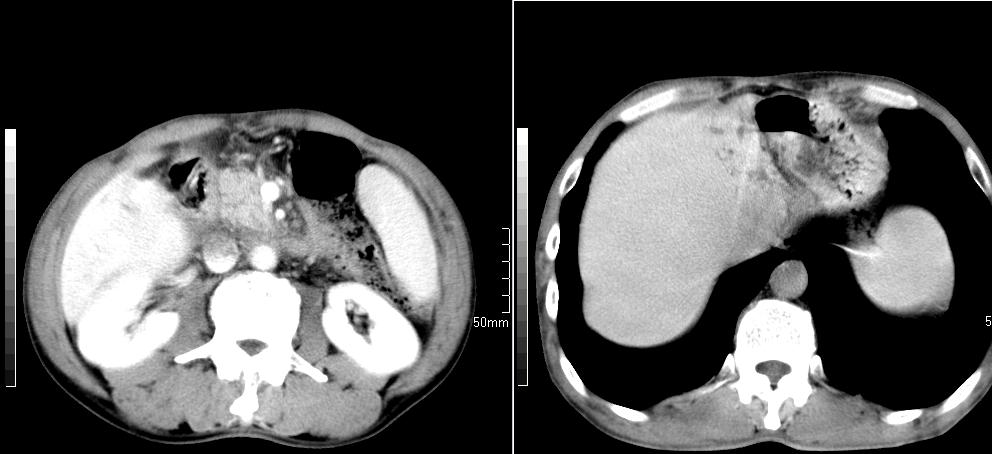

标题: CT26769:男,58岁,腹胀、腹部不适一年余 [打印本页]

标题: CT26769:男,58岁,腹胀、腹部不适一年余

肝右叶后段见小片状略低密度影,边缘不清,轻度强化,内见小血管影通过同,延迟期为等密度,考虑局灶性脂肪浸润。需与血管瘤鉴别。另有胆囊炎、脾大。

肠系膜脂膜炎,胆囊炎,脾大。建议结合临床。鉴别:慢性胰腺炎并假囊肿形成。

1 慢性胰腺炎并假囊肿形成。2 慢性胆囊炎并累及肝边缘!

1)考虑慢性胰腺炎并假性囊肿形成。2) 慢性胆囊炎。3)肝内胆管扩张。

1肝内胆管扩张,性质待定,2慢性胰腺炎胰管扩张,胰腺颈部假囊肿,3肝左叶低密度为小囊肿,4胆囊炎。